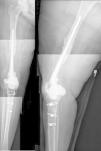

El cemento impregnado con antibiótico, en fase moldeable, se coloca alrededor y dentro del defecto tibial metafisario y unido, si lo hubiera, al vástago tibial, formando un recipiente de cemento capaz de articularse con la cabeza del espaciador. La cabeza del espaciador se utiliza como molde, para lograr una articulación congruente (fig. 3A y 3B). El vástago del espaciador de cadera se inserta en la diáfisis femoral y se cementa en su parte más distal para facilitar la retirada del espaciador en el segundo tiempo. El espaciador de cadera puede ser introducido tanto como sea necesario (fig. 4) para lograr la tensión deseada en las partes blandas y evitar el acortamiento del miembro. La parte más prominente del espaciador puede recortarse según sea necesario. Después de la polimerización del cemento, se evalúan la estabilidad y la amplitud de movimiento (fig. 5).